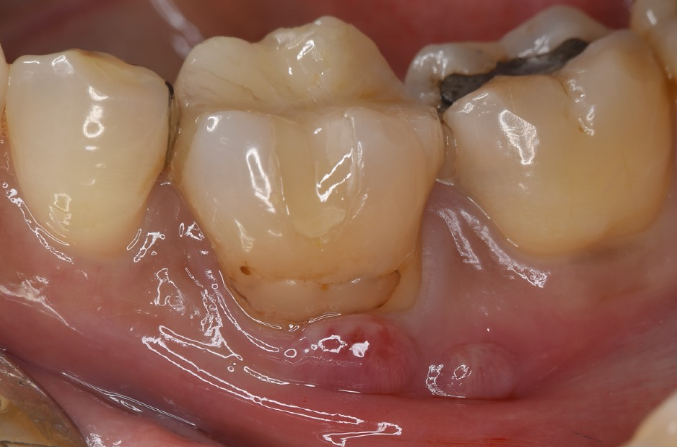

症例1

| 項目 | 詳細 |

|---|---|

| 患者様データ | 56歳 女性 |

| 来院時の主訴 | 「左下の歯茎が下がっていると思っていたら今度は腫れてきた。前医では抜歯と言われた。」 |

| 医院の診断 | 左下第一大臼歯:慢性根尖性歯周炎と重度歯周病の併発、歯肉退縮 左下第二小臼歯・第二大臼歯・第三大臼歯:う蝕 |

| 通院期間 |

1年3か月 |

| 来院回数 | 15回 |

| 治療費 | 総額:650,000円(税抜) 歯周基本治療は保険適用診療 【内訳】 《保険適用診療》 歯周病検査・歯磨きや生活習慣指導・歯石取りクリーニング・第三大臼歯のCR充填 《自費診療》 第一大臼歯:精密根管治療 80,000円、歯根端切除術 100,000円、ファイバーポストコア 20,000円、歯周組織再生療法(歯肉結合組織移植併用) 170,000円、セラミック治療 120,000円 第二小臼歯・第二大臼歯:セラミック治療 80,000円×2 |

| リスクと副作用 | 定期的なメインテナンスが必要、破折リスク、正しい歯磨き習慣が必要不可欠 |

| ここがこだわりのポイント!☝ | 患者様の歯を抜きたくない、という願望に応える為、様々な技術を集結させています。患者様に頑張っていただいた結果、歯周病と合わせて歯茎下がりも改善することができ、治療後に気兼ねなく歯磨きが行えるようになりました。 |